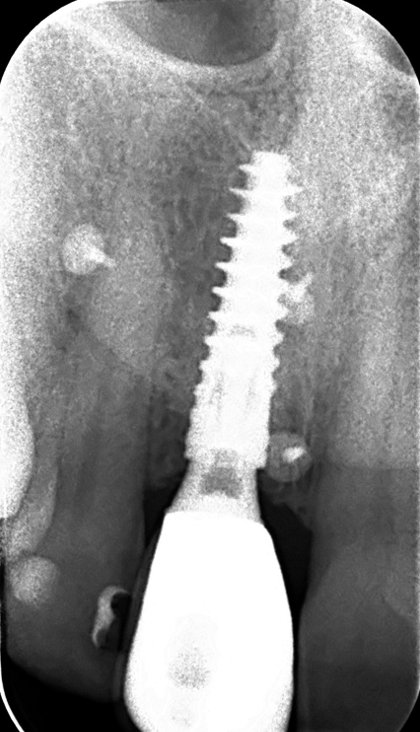

The main issue involved the upper right central incisor (tooth 1.1), which was devitalized and presented recurrent abscesses. Clinical and radiographic evaluation confirmed the presence of buccal bone wall resorption, leading to a significant defect in the alveolar ridge. This condition compromised both the hard tissue and the surrounding soft tissue, posing a challenge for achieving long-term stability and esthetic success in the anterior maxilla.

The surgical protocol began with the atraumatic extraction of tooth 1.1 to preserve as much of the alveolar socket as possible. Immediately following extraction, an N1 implant was placed into the socket using a guided surgical approach to ensure ideal three-dimensional positioning. The “one abutment one time” technique was applied to minimize soft tissue manipulation during the healing phase, which is particularly important in esthetic areas.

Given the significant buccal defect, guided bone regeneration (GBR) was performed simultaneously. A mixture of autologous bone and creos™ xenogain™ was applied to the defect and covered with a resorbable creos™ membrane to restore ridge width and support the buccal contour. In addition, a connective tissue graft was harvested and placed in the vestibular region to increase the thickness of keratinized mucosa. This combined approach addressed both hard and soft tissue deficiencies, providing the biological foundation for a stable and esthetic outcome.